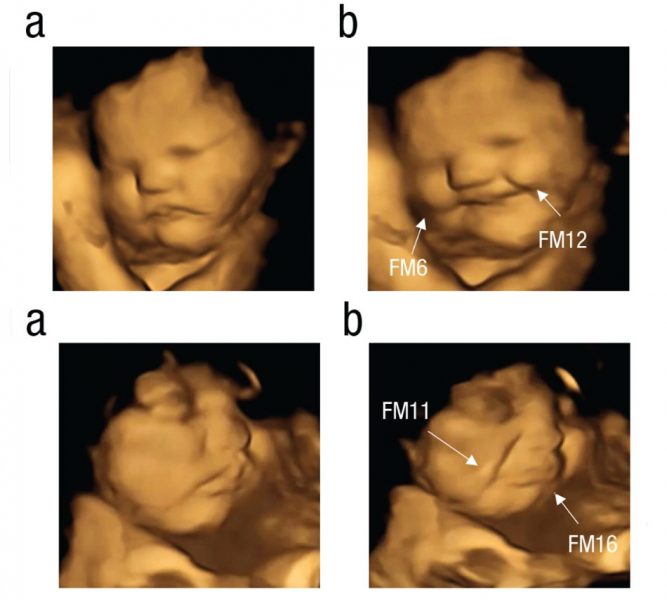

Los expertos explican que se produjeron respuestas que parecían mostrar una cara de satisfacción (risa) y una cara de llanto (quizá rechazo). Los fetos que fueron expuestos al sabor de las zanahorias tuvieron una respuesta de cara de satisfacción, en cambio, los que fueron expuestos al sabor de la col rizada mostraron una cara de llanto. Los investigadores explican que los seres humanos experimentan el sabor a través de una combinación de gusto y olfato, en el caso de los fetos, esto se produce cuando inhalan y tragan el líquido amniótico.

Hay que destacar que las ecografías 4D se han convertido en una herramienta de importancia para monitorear a los futuros bebés, en especial en el campo de la investigación, para comprender cómo responden ante comportamientos maternos como el hábito de fumar o beber, pero también en lo referente a la salud mental de la madre, como la ansiedad, la depresión o el estrés. Ahora han ayudado a obtener evidencias directas y comprender mejor las habilidades fetales para sentir y discriminar diferentes sabores y olores de los alimentos ingeridos por sus madres.